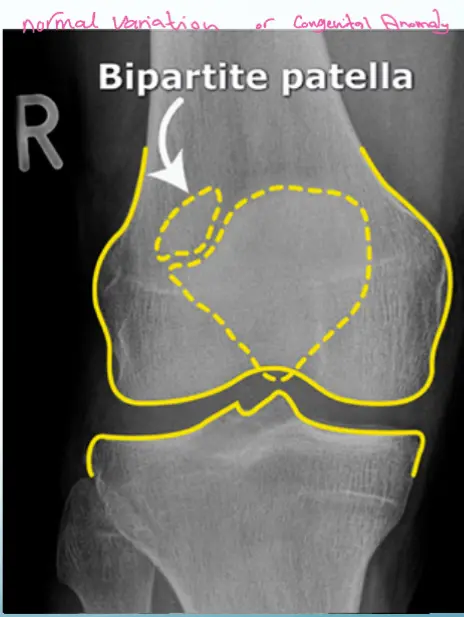

Patient: 26âyearâold male who fell while running.

External findings: superficial anterior abrasions, but full range of motion retained.

- Upperâlateral corner of the patella

- Line not as sharp as a fresh fracture

- Area not clearly tender

- Full ROM (consistent with the overall exam)

- Trauma insufficient to cause a definitive fracture

Bipartite Patella - Normal Variant

- No localized tenderness

- Superolateral

- Line not that of a fresh fracture